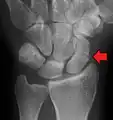

A subtle scaphoid fracture

A more obvious scaphoid fracture on a scaphoid view X ray

Radiolucency around a 12 days old scaphoid fracture that was initially barely visible.[13]